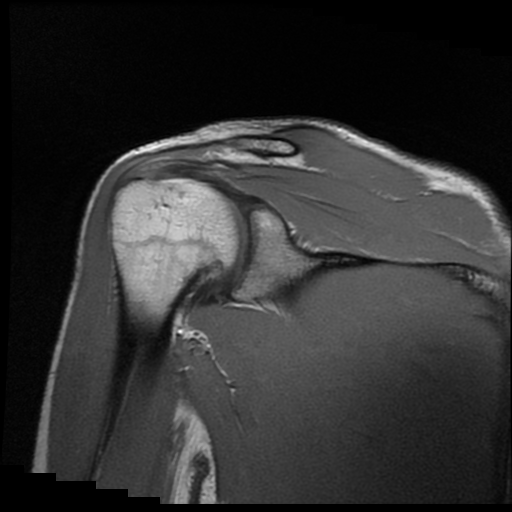

TECNICA EMPLEADA

Se coloca al paciente en decúbito supino, utilizando bobina dedicada de 8 canales, obteniendo imágenes en planos axial, sagital y coronal, secuencias, Spin Echo, Eco de Gradiente, potenciadas a Densidad de Protones, con pulsos de saturación de grasa.

HALLAZGOS IMAGENOLOGICOS

Lesión post traumática de Hill Sachs a nivel de la cabeza humeral, tendinosis aguda del supra espinoso.

La lesión de Hill-Sachs es un defecto de impactación en la región posterosuperolateral de la cabeza humeral, secundario a luxación o subluxación anterior del hombro. Se produce cuando la cabeza humeral, desplazada anteroinferiormente, colisiona y se “muerde” contra el borde anteroinferior de la glenoides.